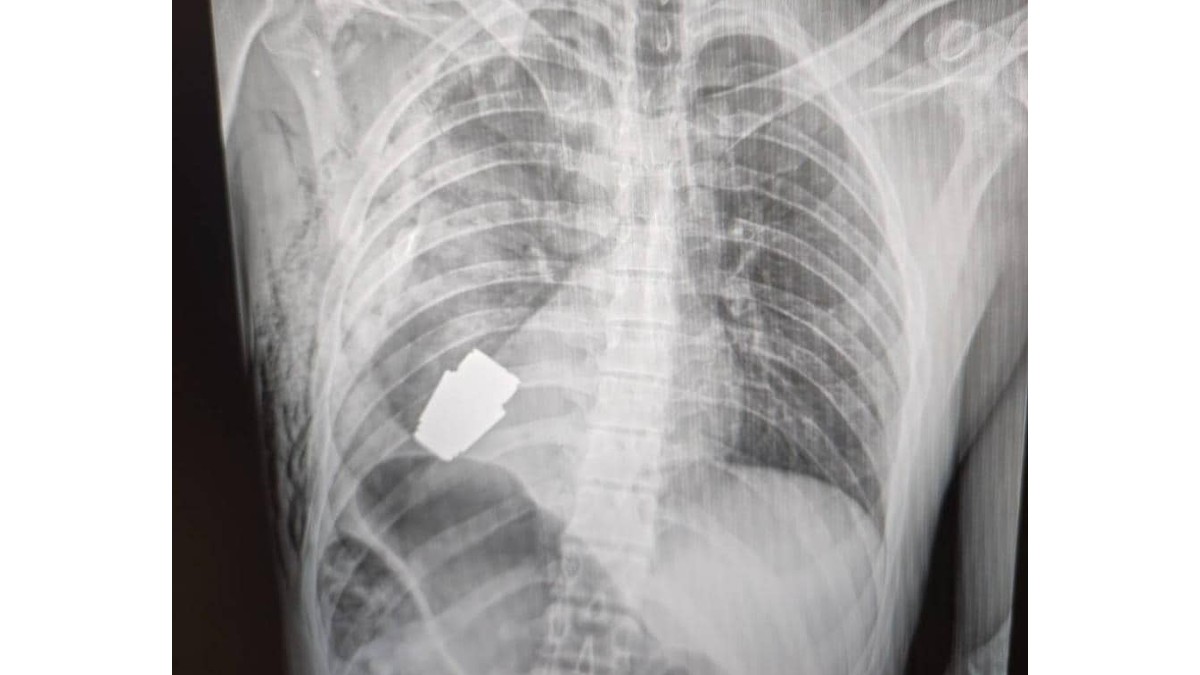

मीडिया रिपोर्टों के अनुसार, 9 जनवरी को यूक्रेन की उप रक्षा मंत्री, हैना मालियार ने फेसबुक पर एक एक्स-रे इमेज पोस्ट की। इस इमेज में यूक्रेन के एक सैनिक के सीने के अंदर जिंदा ग्रेनेड दिखाया गया था। लाइव साइंस की रिपोर्ट के अनुसार, डॉक्टरों ने उस ग्रेनेड को हटाने के लिए एक ऑपरेशन किया। अगर वह सैनिक की शरीर में ही फट जाता तो आप अंदाजा लगा सकते हैं कि क्‍या हो सकता था।

Live Grenade Surgery : मरीज के सीने से जो ग्रेनेड हटाया गया वह लगभग 1.6 इंच लंबा था। इस तरह के ग्रेनेड लक्ष्य से 400 मीटर दूर से ग्रेनेड लॉन्‍चर के जरिए दागे जा सकते हैं।

मरीज के सीने से जो ग्रेनेड हटाया गया वह लगभग 1.6 इंच लंबा था। इस तरह के ग्रेनेड लक्ष्य से 400 मीटर दूर से ग्रेनेड लॉन्‍चर के जरिए दागे जा सकते हैं। बताया जा रहा है कि सर्जरी के दौरान डॉक्‍टरों ने इलेक्ट्रोकोएग्यूलेशन (electrocoagulation) का इस्‍तेमाल नहीं किया। यह रक्तस्राव को कंट्रोल करने का एक नॉर्मल तरीका है, जिसमें इलेक्ट्रिक कंरट का इस्‍तेमाल होता है। डॉक्‍टरों को डर था कि इलेक्ट्रिक करंट यूज करने पर ग्रेनेड फट सकता है।